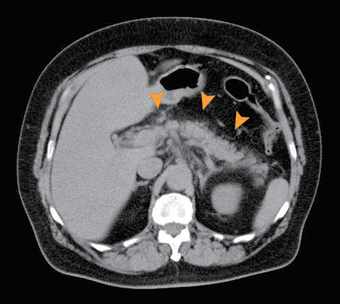

【急性膵炎】

膵臓の炎症がその周囲組織に波及している。